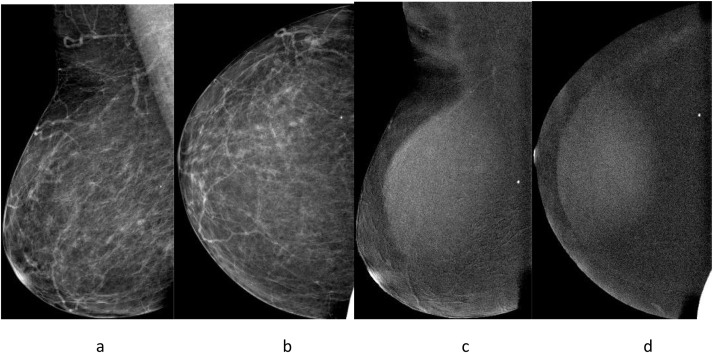

Diagnostic performance of contrast-enhanced spectral mammography compared to conventional mammography across varying breast densities

This study retrospectively included 326 adult female patients. The study protocol was pre-registered on the Open Science Framework (OSF) platform. Each image was annotated and evaluated by a minimum of two expert radiologists, while …